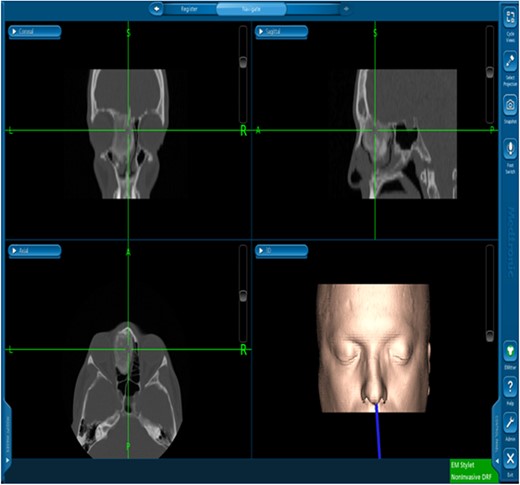

The patient underwent image-guided endoscopic endo-nasal removal (Fig. 5) of a large fibro-osseous tumor, the tumor was adherent to the orbit and skull base which was removed (Fig. 6). The resected tumor was sent to the histopathological examination, which confirmed the final diagnosis of fibrous dysplasia. The patient remained free of symptoms with no recurrence for 3 years after the resection.

Image-guided endoscopic tumor removal from orbit and skull base.